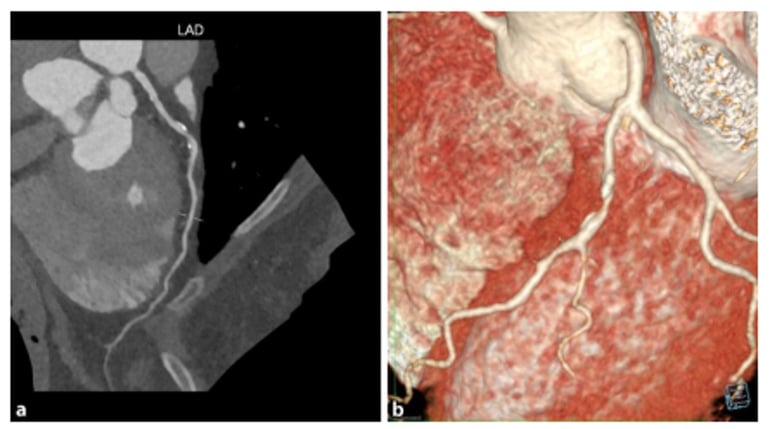

Example of a sufficiently good examination. Good contrast in the coronary arteries. The heart is displayed without steps.

Another example after 3D post-processing (obligatory vessel and volume display): The coronary vessels are clearly and continuously displayed. Image source: Rolf et al. 2023